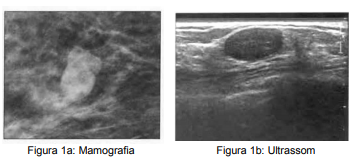

A.J.A.C. 42 anos, feminino, procura mastologista devido à alteração em exame mamográfico de rastreio BI-RADS® 0 (imagem 1a). Realiza complementação diagnóstica com ultrassonografia de mamas que apresentou o seguinte achado (imagem 1b). Ao exame físico, paciente não possui qualquer alteração em mamas. De acordo com os achados da imagem, assinale a alternativa correta que apresenta a classificação do BI-RADS® ultrassonográfico e conduta adequada.